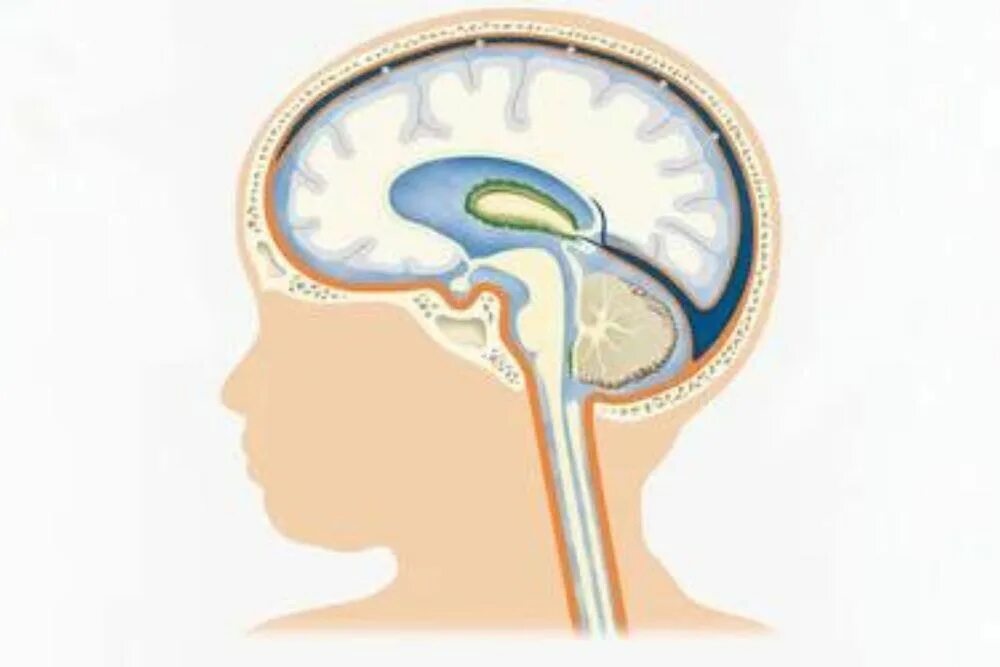

Умеренно выраженной наружной гидроцефалии у взрослых